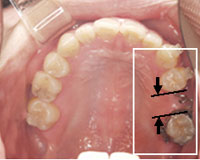

ブリッジを外したところ

しかし、もうこれ以上歯を削りたくないというご希望があり、インプラント治療を希望される。しかし、インプラントを入れるには前後に十分な隙間がないため吉本歯科医院では、インプラントを入れる為に、二箇所の隙間を一箇所に集める部分的な矯正を行い、インプラントが入るスペースを作ってからインプラント治療を行う。

抜けている所にインプラントを入れる為部分的な矯正を行い、隙間を一箇所にまとめインプラントが入るスペースを作ります